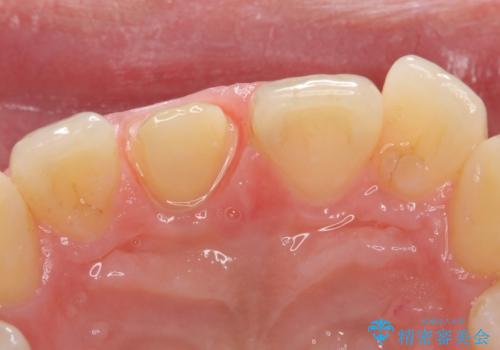

オールセラミッククラウン 痛みの引かない歯の治療

- 他院にて根管治療を行っていたが、痛みが引かないので診て欲しいといらっしゃった方の症例です。

マイクロスコープ下でラバーダムを使用しながら根管治療を行い、痛みが治まった後にオールセラミッククラウンによる補綴を行いました。